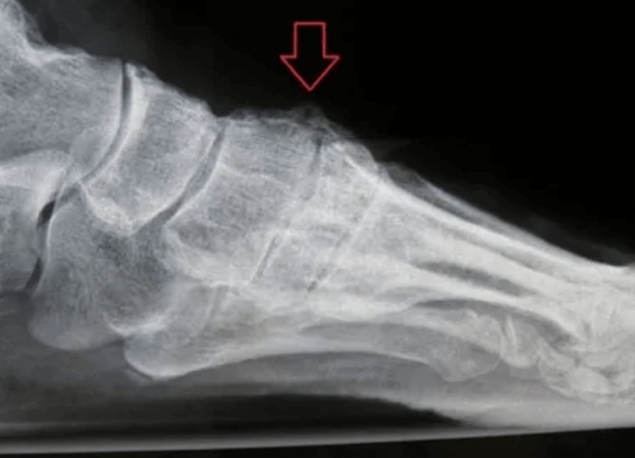

Figure 2: Animation depicing the bone spur/exostosi removed after the procedure

Figure 3: Intraoperative picture showing the joint arthritis, cartliage wear and bone spurs at the joint.

Figure 4: Intra-operative picture showing the exostosis/bone spurs cleaned up, a smooth bone surface and a gap between the two bones.